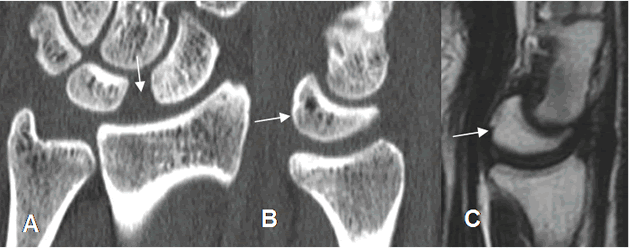

Fig 73. Inestabilidad tipo DISI.

A: TAC reconstrucción coronal. Aumento del espacio escafolunado, por ruptura ligamentaria.

B: TAC reconstrucción sagital y C: RM sagital en T2. Angulación anterior del lunado, por inestabilidad tipo DISI.